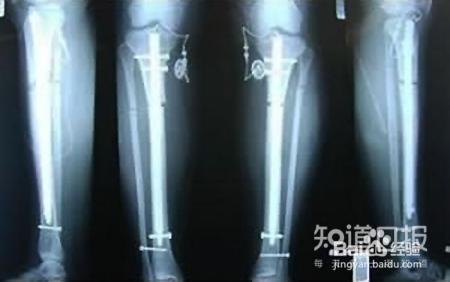

接受断骨增高术后的腿骨X光照片,图片来源于网络

对生理学有些了解的朋友,肯定知道人体的某些组织是可以再生的,比如骨骼。当因外伤等情况引起骨骼断裂时,在骨骼中,一方面通过破骨细胞吞噬、清除死骨,另一方面通过细胞分裂产生新的软骨和骨,直至痊愈。那么,断骨增高术是怎么回事呢?

断骨增高术,其实就是肢体延长术。肢体延长术在临床上并不罕见,原理是将患者的骨头锯断,人为拉长,迫使骨细胞增殖。其手术指证是外伤、肿瘤、感染等原因所致的骨缺损或肢体不等长。这是一种风险很大的手术。首先,它对患者的体质要求很高,不是谁都能做的。其次,不管是手术过程还是术后的康复护理都需要极高的技术水平。稍有不慎,就有可能导致截肢、瘫痪,乃至由感染而死亡。

由于人们对个人形象越来越看重,加之一些不法美容院的宣传,片面强调断骨增高术的好处,使得很多患者轻信之下做尝试,产生了极其恶劣的社会影响,因此致残者不在少数。有鉴于此,卫生部于2006年下发了《关于对“肢体延长术”实施严格管理的通知》,再次重申严禁将断骨增高术用于美容项目。[9]